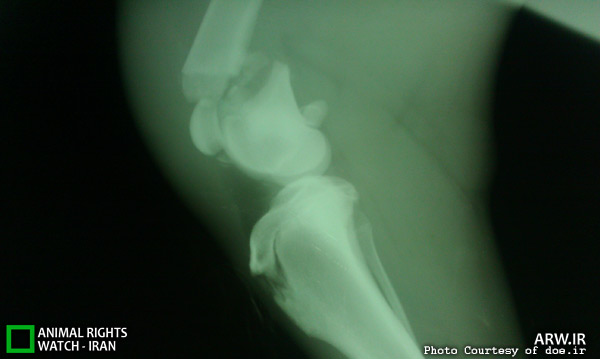

به گزارش روابط عمومي حفاظت محيط زيست استان فارس، مهندس ابراهيمي كارنامي، مدير كل حفاظت محيط زيست فارس گفت:براساس اعلام گزارش مردم محلي در شهرستان آباده پس از وقوع حادثه برخورد اتومبيل با يك قلاده گرگ، بلافاصله مامورين يگان اجرايي حفاظت محيط زيست به محل حادثه اعزام و گرگ مذكور را كه از ناحيه ران به شدت آسيب ديده بود با همكاري ارگانهاي دامپزشكي وآتش نشاني به اداره محيط زيست شهرستان خرم بيد منتقل و در نهايت با هماهنگي لازم به مركز اداره كل اعزام نمودند. پس ازانجام معاينات اوليه توسط دامپزشك اداره كل و عكسبرداري از گرگ آسيب ديده شكستگي قسمت انتهايي استخوان ران مشخص شد.

سپس تيم جراحي متشكل از دامپزشكان مجرب پروفسور دهقان ، آقايان دكتر وصال، رعايت و هومن تشكيل و عمل جراحي بر روي گرگ مذكور صورت گرفت.

ابراهيمي كارنامي افزود:در اين عمل جراحي كه به مدت 3 ساعت به طول انجاميد.از شيوه هاي نوين جراحي دامپزشكي استفاده و در نهايت اولين جراحي تخصصي ارتوپدي در ايران بر روي يك قلاده گرگ با موفقيت انجام شد.